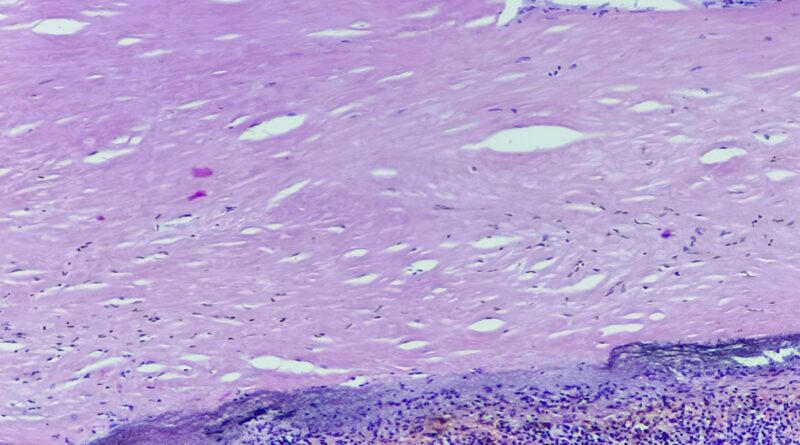

Pacjent 43 letni przyjęty w trybie planowym na Oddział Ortopedii z powodu wielomiesięcznego narastającego bólu, tkliwości, obrzęku i zmniejszenia ruchomości

Czytaj więcej